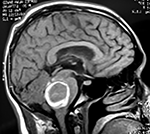

EJEMPLO DE CASO CLÍNICO (8)

Paciente femenino de 29 años de edad con historial de cefalea crónica que presenta súbitamente disdiadococinesia y dismetría izquierda.

El estudio de RMN presenta una lesión bien circunscrita en hemisferio cerebeloso izquierdo con periferia de predominio hiperintenso en T1 y T2, y centro hipointenso, edema perilesional mínimo, así como una imagen de un vaso venoso alimentador que recorre hacia el ángulo pontocerebeloso izquierdo.

Se realizó una craniectomía suboccipital paramedial derecha, así como un abordaje transcortical en el hemisferio cerebeloso izquierdo llegando a la región perilesional de aspecto amarillento, posteriormente se observa una lesión oscuro-verdoso de contenido hemático antiguo, retirando la cápsula y su contenido en la totalidad.

La evolución clínica de la paciente fue satisfactoria solo preservando la dismetría como secuela.

El resultado histopatológico fue consistente en angioma cavernoso.

El estudio de control de RMN se observa la brecha quirúrgica y ausencia de lesión (figs. 1, 2 y 3).

Figura 1:

Lesión cerebelosa izquierda ponderaciones en T1 y T2, la flecha señala vaso nutricio hacia el ángulo pontocerebeloso izquierdo, se puede observar el centro de intensidad heterogénea con contenido quístico multiloculado y edema perilesional leve.